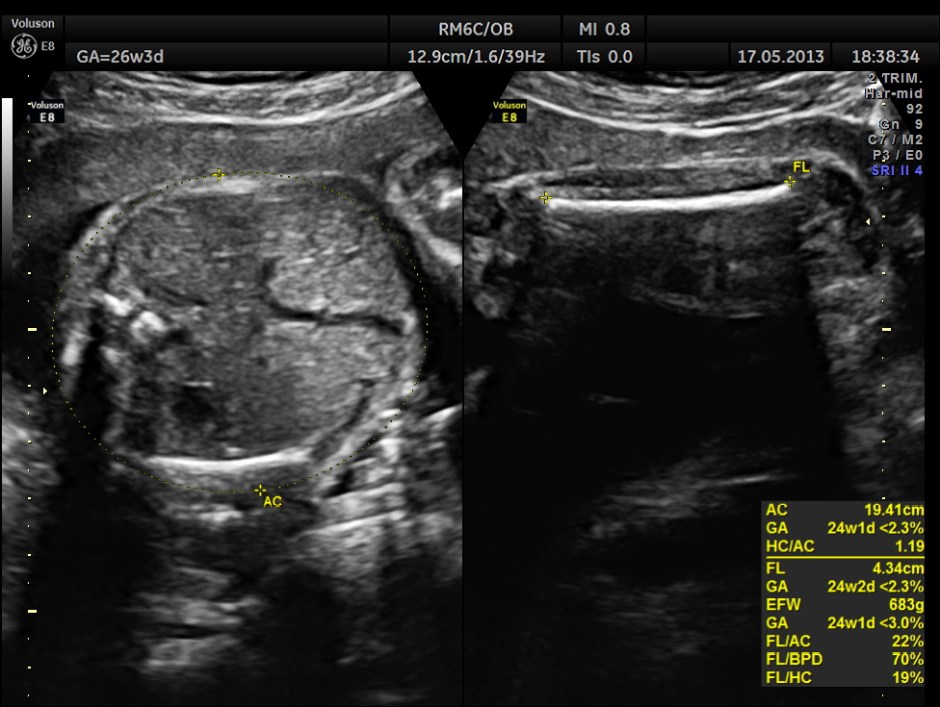

This was a 20 year old primi gravida on treatment for long standing seizure disorder ; she was on tab carbamazepine 200 mgm twice daily for a long time . The scan was done around 26 weeks of gestation.

The images are given below.

The abdominal images are given below.

The limbs are shown below.